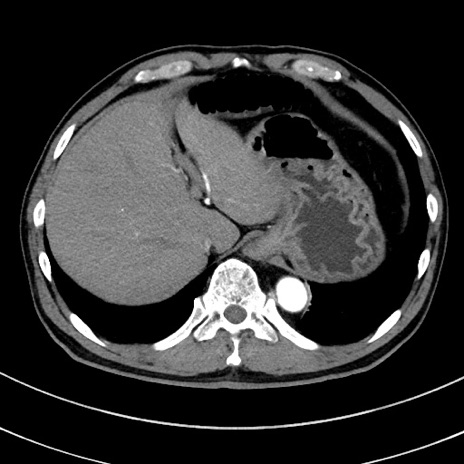

症例8(横断像)

【症例】 60歳代男性

【主訴】 黒色吐物

【現病歴】 4日前から嘔気自覚、2日前の朝食後にも嘔気あり、自分で手で嘔吐反射起こし嘔吐したところ血が混ざっていたため受診。

【既往歴】 5年前汎発性腹膜炎を伴う急性虫垂炎で手術、高血圧、前立腺肥大症、高脂血症

【身体所見】 腹部正中に手術癩痕あり 腹部平坦・軟圧痛なし膨満感あり

【データ】WBC 8400、CRP 4.54